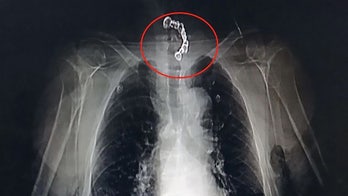

Surgery October 31, 2019 Man nearly chokes to death on dentures after accidentally swallowing them during meal His family estimates that the dentures had been lodged in his throat for up to eight hours.